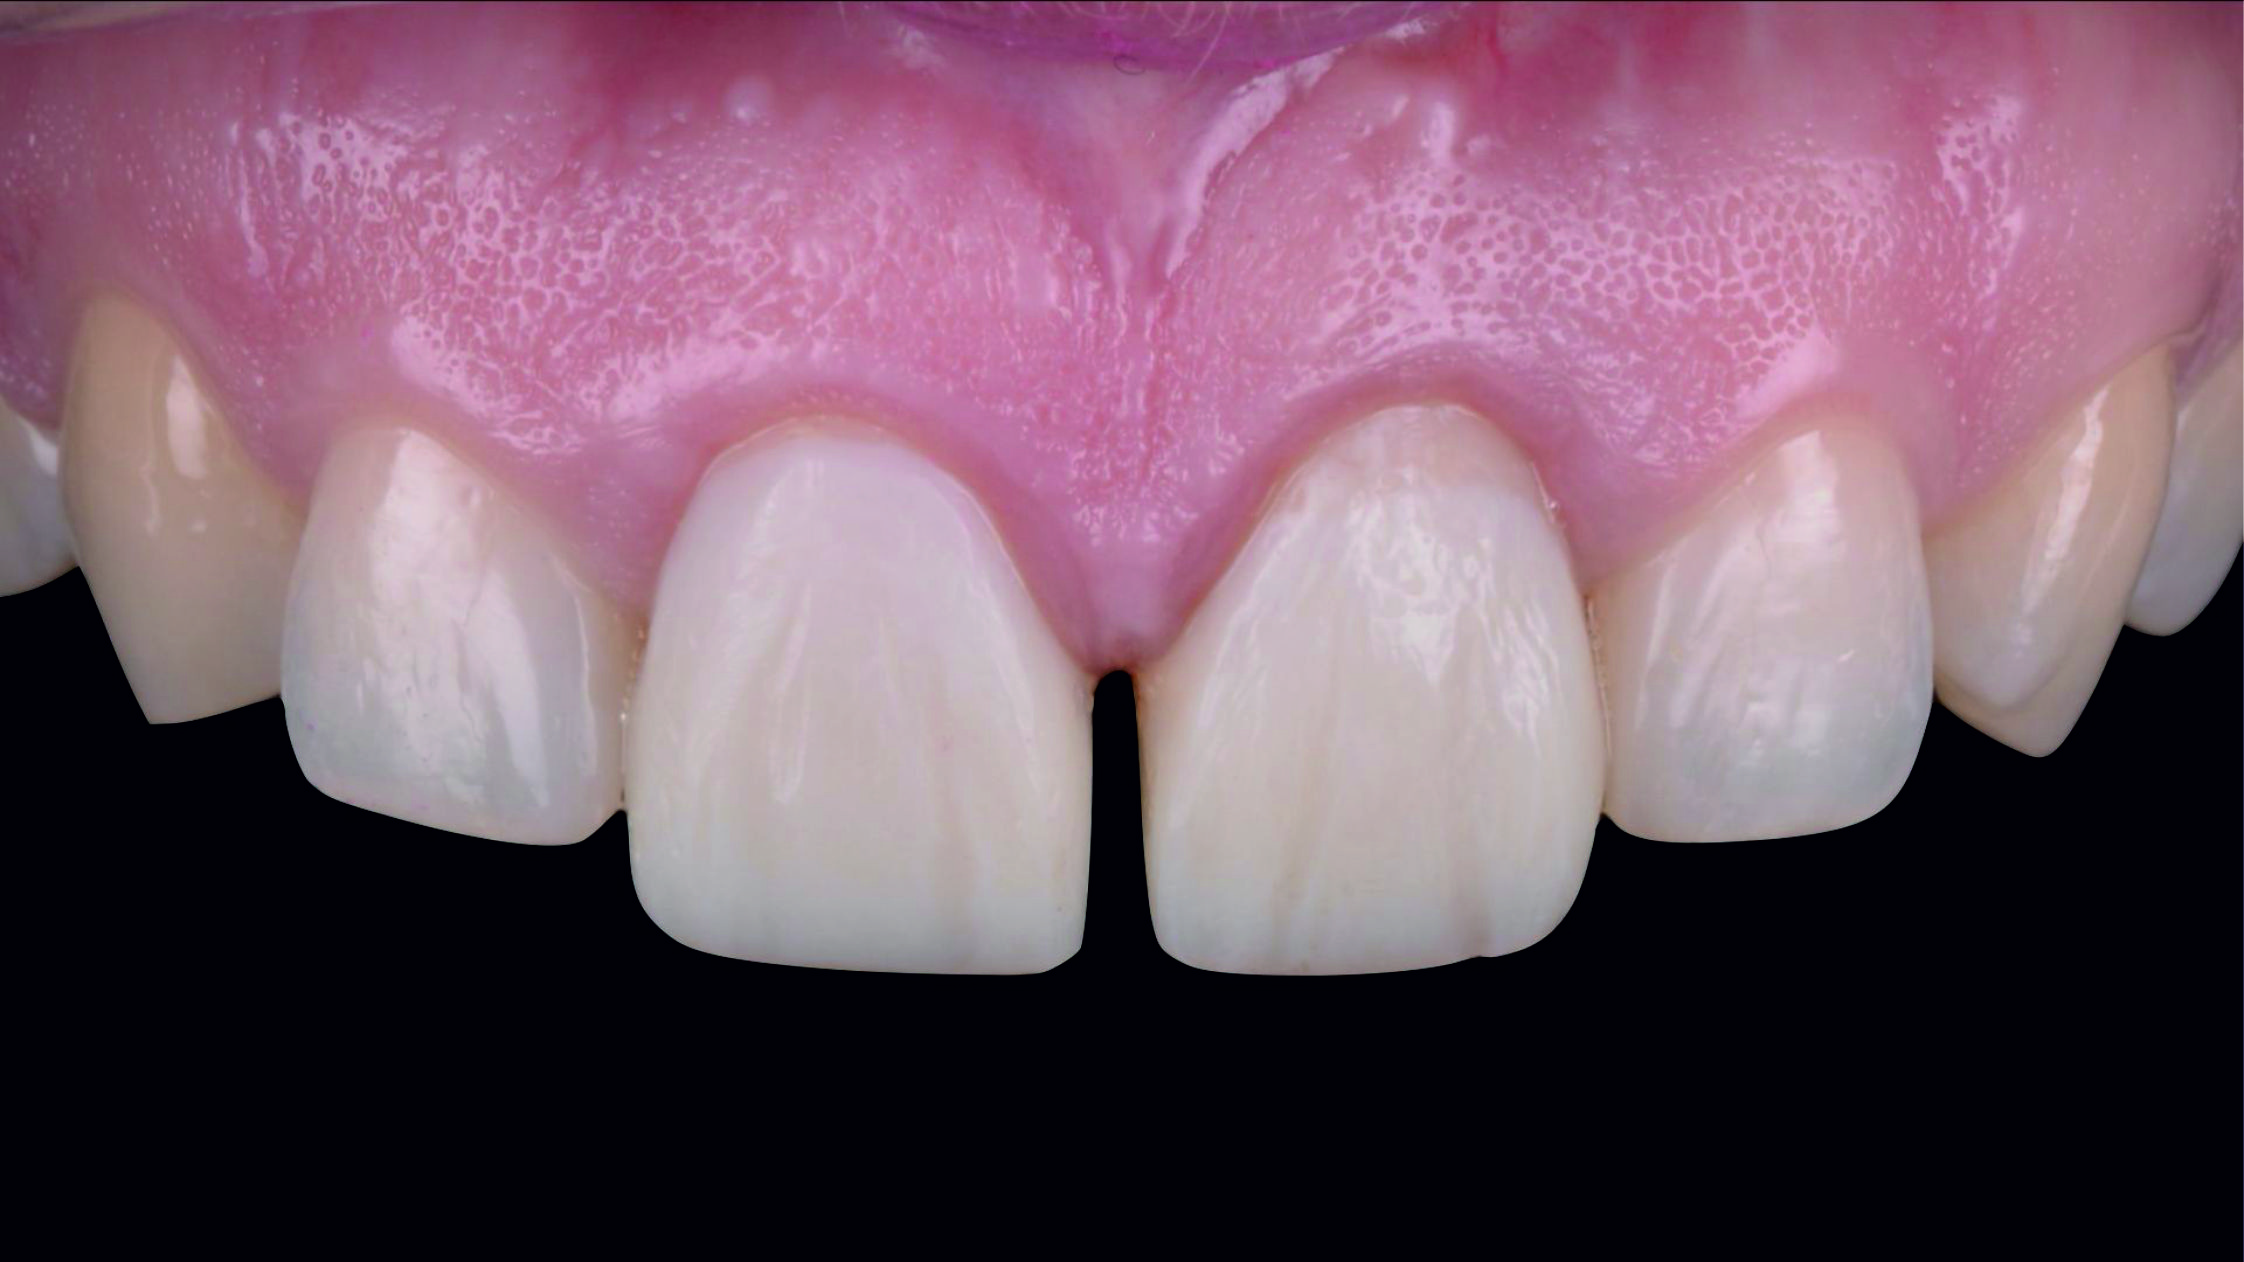

Фото 1. Початкова ситуація: жінка віком приблизно 35 років, із двома металокерамічними коронками, встановленими на верхніх центральних різцях.

Основні скарги: асиметрія центральних різців, запалення й кровоточивість ясен навколо коронок, загальне невдоволення естетикою цієї зони.

Фото 2. Через високо розташовану лінію посмішки можна припустити, що будь-яка вада після лікування обов'язково буде дуже добре помітною.

Фото 3. Внутрішньоротовий вигляд початкової ситуації.